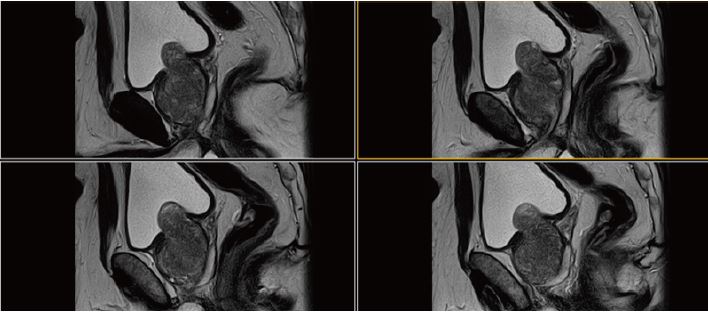

Рис. 1.  Сагітальне, Т2-зважене зображення.

Рис. 2. Аксіальне, Т2-зважене зображення (за протоколом mpMR).

Рис. 5. Сагітальне,  Т2-зважене зображення.

Рис. 6. Аксіальне, Т2-зважене зображне (за протоколом mpMR).

Рис. 9. Сагітальне, Т2-зважене зображення.

Рис. 10. Аксіальне, Т2-зважене зображення (за протоколом mpMR).

Рис. 13. Сагітальне, Т2-зважене зображення.

Рис. 14. Аксіальне, Т2-зважене зображне (за протоколом mpMR).